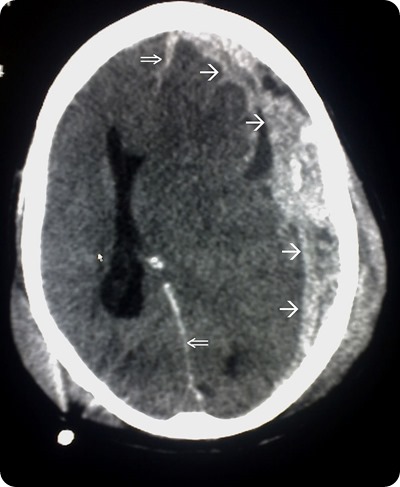

Neuroimaging is a key technique in terms of diagnosing SBS. Intracranial pathologies such as cerebral edema and subdural and subarachnoid hemorrhage may be identified with the help of CT scans. These scans are usually the tool of choice in emergency situations.

Head trauma CT scan

CT scan flowing head trauma, the single arrows mark the spread of the subdural haematoma and the double arrows mark the midline shift. Source: commons.wikimedia.org